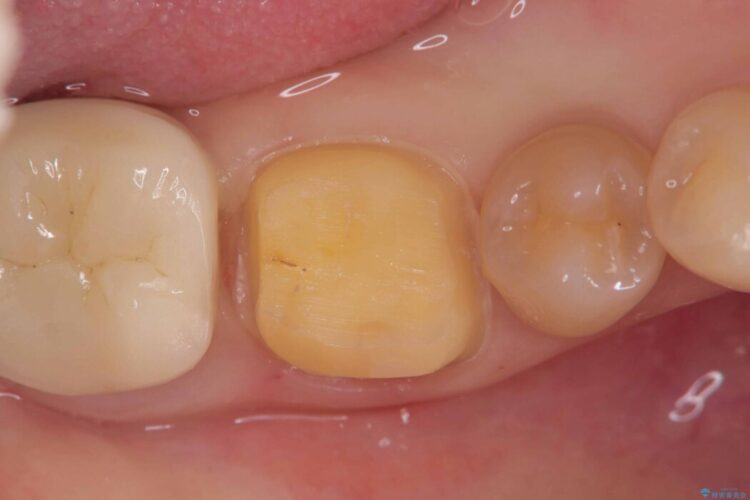

噛む面や外側にも過去の詰め物が入っている状態で、このように詰め物の範囲が大きいと治療後に歯が割れてしまうリスクが高くなります。

今回は歯の強度と将来的な破折リスクを考慮し、セラミッククラウンによる治療を行うこととしました。